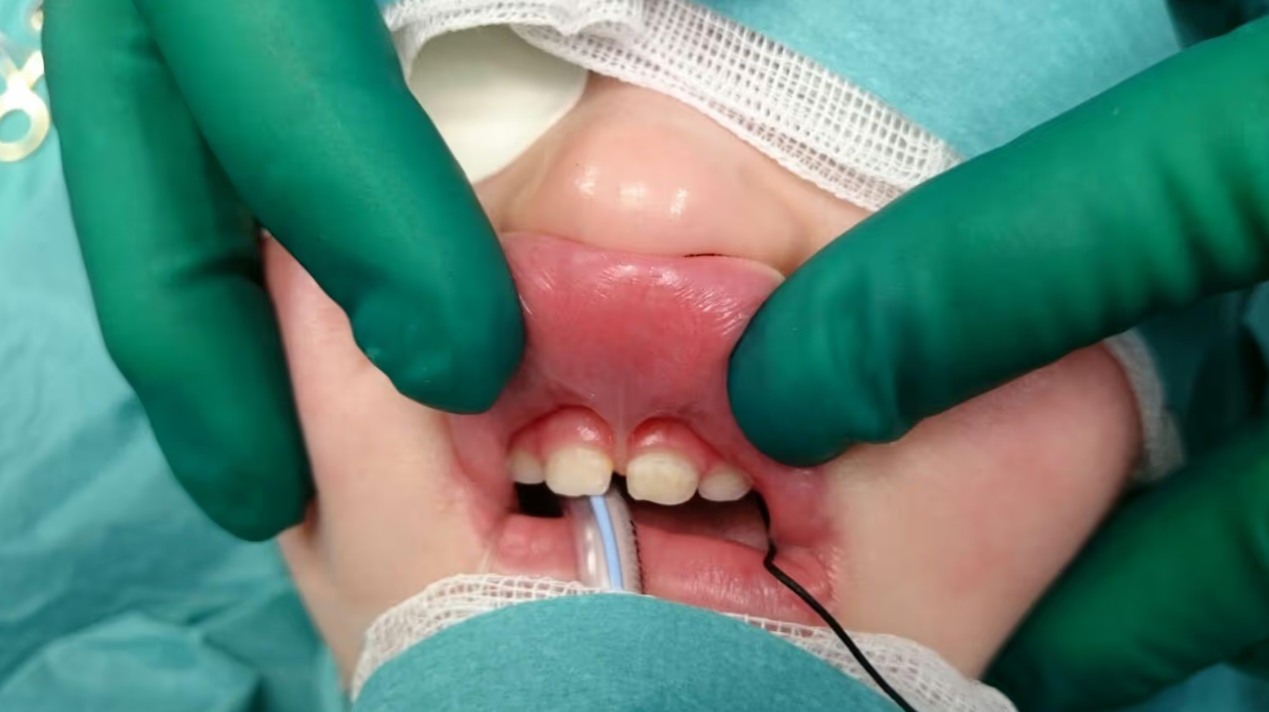

In der Praxis von DDr. Pamela Österreicher in Hollabrunn wird die Durchtrennung des Lippen- oder Zungenbändchens als kleiner, ambulanter Eingriff unter lokaler Betäubung durchgeführt – bei Kindern auf Wunsch auch mit Lachgasunterstützung, um eine angstfreie Atmosphäre zu schaffen.

Zunächst wird das Areal sanft betäubt. Anschließend wird das Band mit wenigen präzisen Schnitten durchtrennt beziehungsweise entfernt. Häufig wird dabei eine sog. VY-Plastik angewandt. Die Wunde wird – je nach Technik – fein vernäht oder offen belassen, was meist eine schnellere Heilung ermöglicht. Der Eingriff dauert nur wenige Minuten und wird meist als nahezu schmerzfrei empfunden.